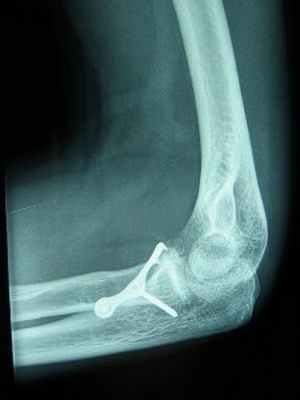

При переломе венечного отростка остеосинтез выполняют 3,5 мм винтом. Для остеосинтеза перелома головки лучевой кости применяют фиксацию малым спонгиозным винтом.

Остеосинтез головки лучевой кости и венечного отростка локтевой винтами.

При переломах диафиза и метафиза обеих костей или изолированных переломах лучевой и локтевой костей остеосинтез производят прямыми узкими, желобоватыми пластинами.

Принципы экстракортикального остеосинтеза костей предплечья.

Остеосинтез при переломах дистального отдела лучевой кости производят редко, как правило, при неудаче консервативного лечения. Для остеосинтеза применяют малую Т-образную пластину (Рис. 140).